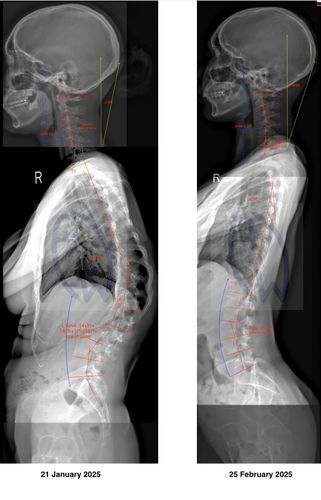

Understanding Scoliosis

Scoliosis Awareness Program